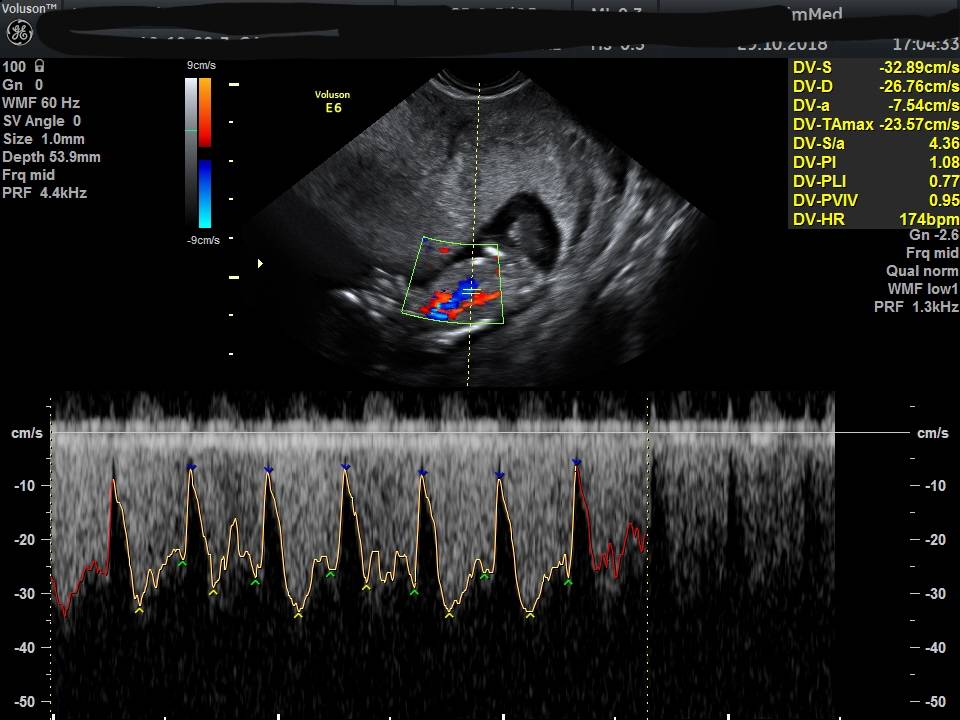

Kochane to moja dzidzia niestety na zdjeciu ktore wyslalam na grupe fb nie widza. Myslicie ze zdjecie nr 2 jest lepsze?